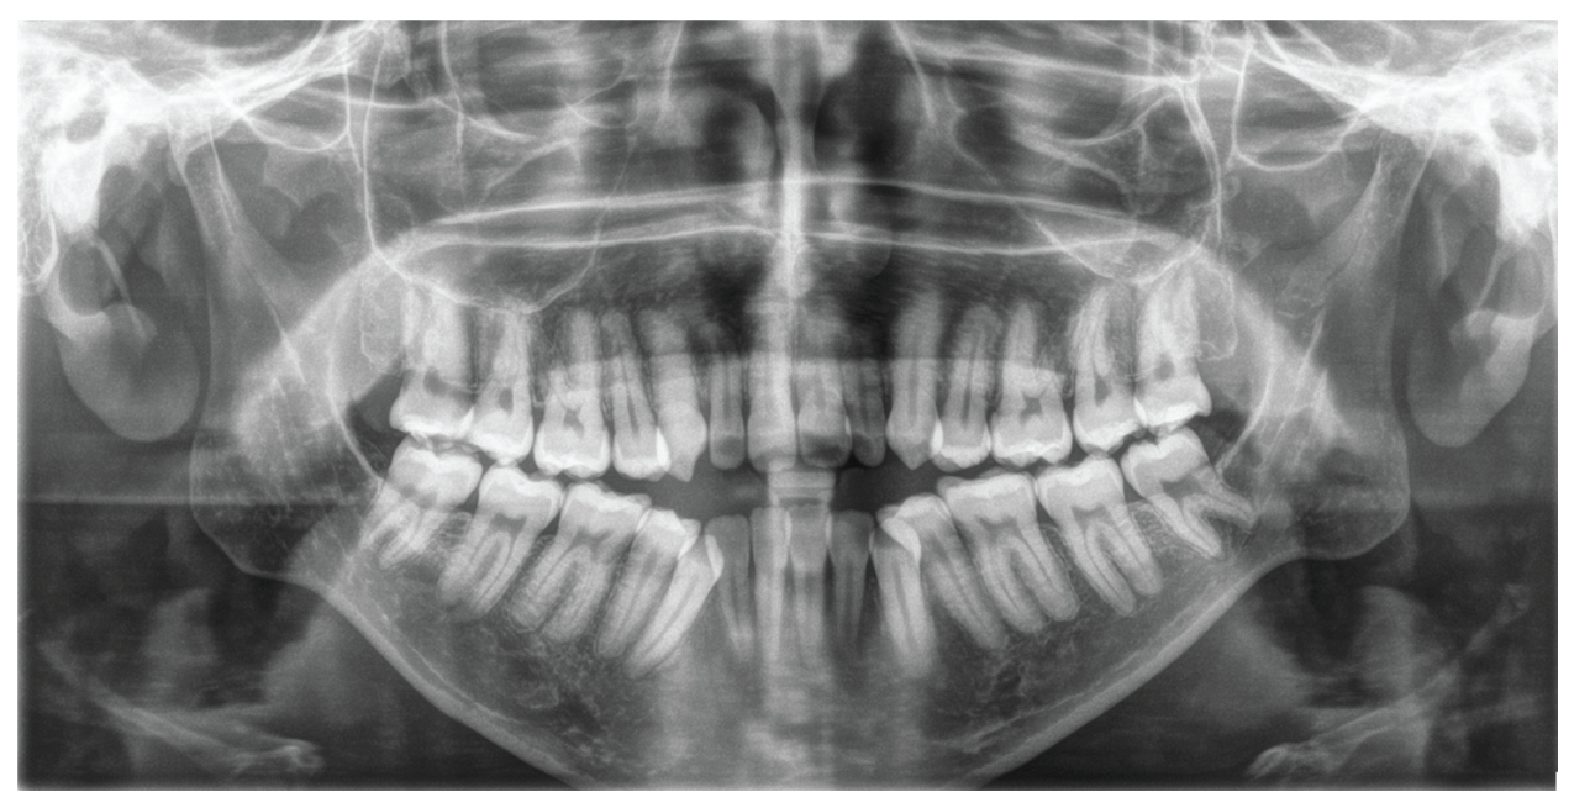

Figure 3: Panoramic radiography of a patient with Nemaline Myopathy. Initial panoramic radiograph shows all teeth fully developed, the absence of 4 premolars, rounded dental roots, long and narrow condylar neck, short coronoide process, marked antegonial notch. All teeth were fully developed. The mesial inclination of the maxillary and mandibular posterior teeth was prominent, typical of anterior open bite cases.